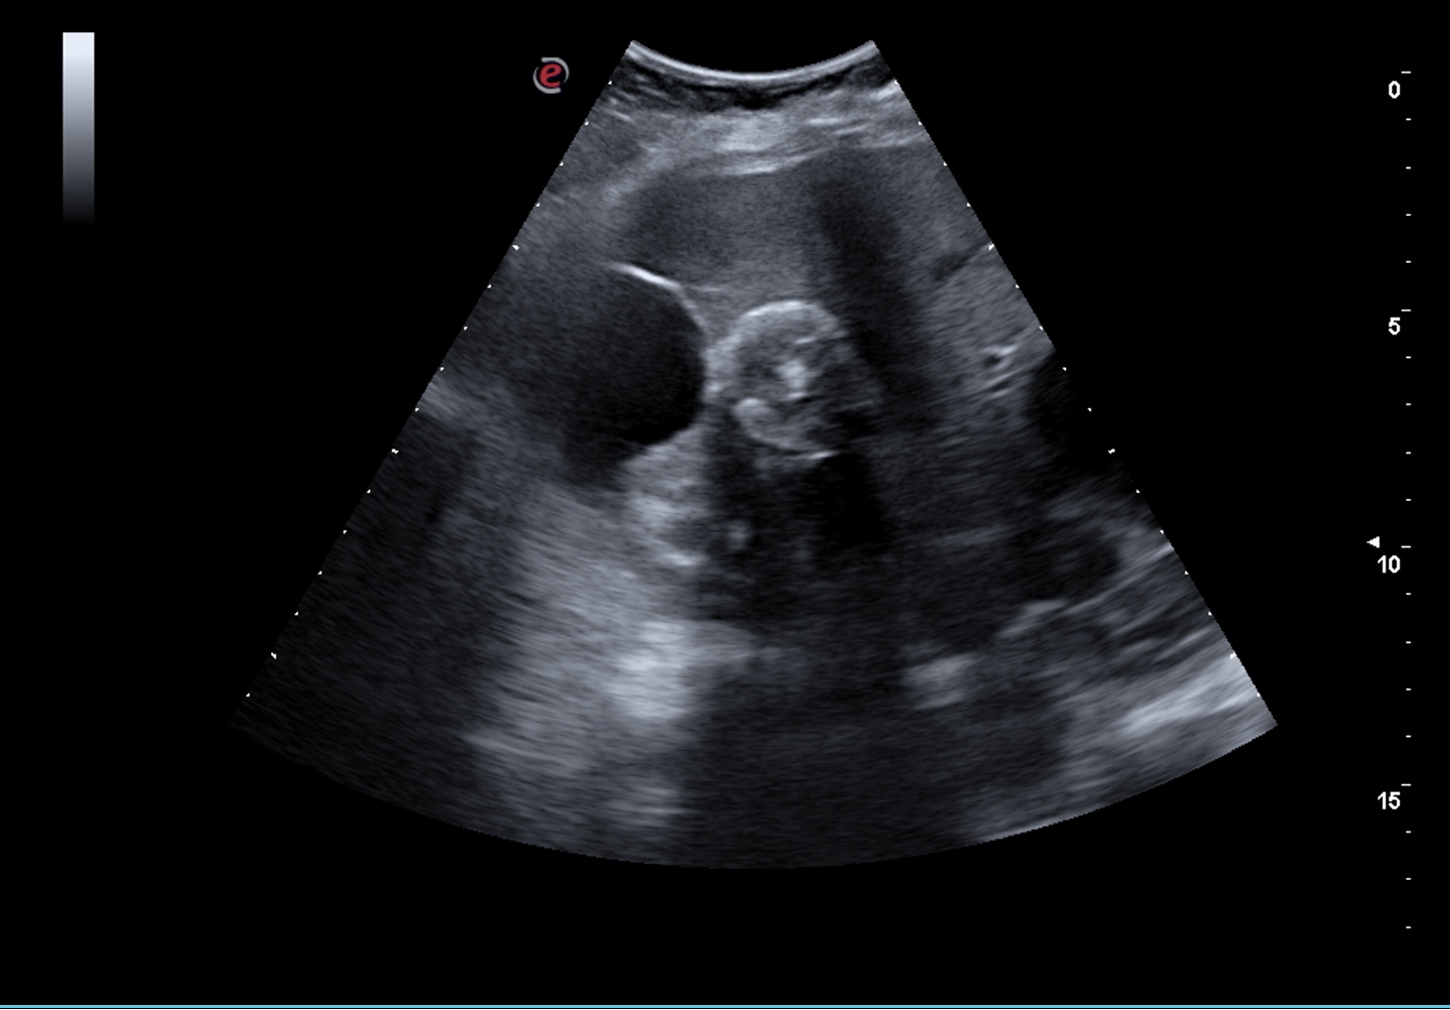

Hallazgos ecográficos

Ecografía: Hígado aumentado de tamaño con presencia de múltiples quistes simples (> 8), algunos de ellos tabicados, el mayor de 62 mm, con presencia de imagen heterogénea calcificada sin vascularización central ni periférica en lóbulo hepático derecho, segmento V-VI de 34 mm. Páncreas parcialmente visualizado sin lesiones. Riñón derecho con presencia de quiste cortical simple de 52 mm, sin otras lesiones, sin ectasia. Riñón izquierdo de tamaño y morfología normal sin lesiones, sin ectasia. Bazo sin alteraciones de tamaño normal. Vejiga adecuadamente replecionada con paredes levemente engrosadas, residuo postmiccional 30 ml.